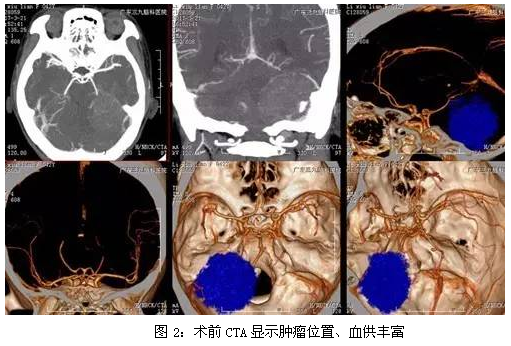

李女士,女性,42岁,3年前出现耳鸣未引起重视,近期外院就诊,CT显示桥小脑角占位性病变,为求进一步治疗,来我院就诊。入院后完善相关检查,术前CT显示左侧桥小脑角区稍高密度影,大小约51mm×34mm×36mm,术前CTA显示肿瘤位置、血供丰富,磁共振检查结果提示左侧后颅窝占位性病变,完善术前准备后,于全麻下行左侧CPA区脑膜瘤切除术,手术由神经外一科主任张良主刀完成,手术过程顺利,术后磁共振提示肿瘤切除。

所有病例均行颅脑CT及MR扫描。CT平扫提示CPA区可见等密度或略高密度占位性病变,边缘清晰,呈卵圆形,基底部较宽,偶见瘤内钙化。MR扫描提示等T1或稍长T1、 等T2或稍长T2改变,也可为混杂信号,增强后明显均一强化,边界清楚,呈圆形或卵圆形。部分内有囊变及钙化,脑膜尾征明显。病理结果本例病变大小约47×41×41mm,为巨大脑膜瘤,各序列呈偏等信号影,中心强化程度较周边低,脑膜尾征不明显。